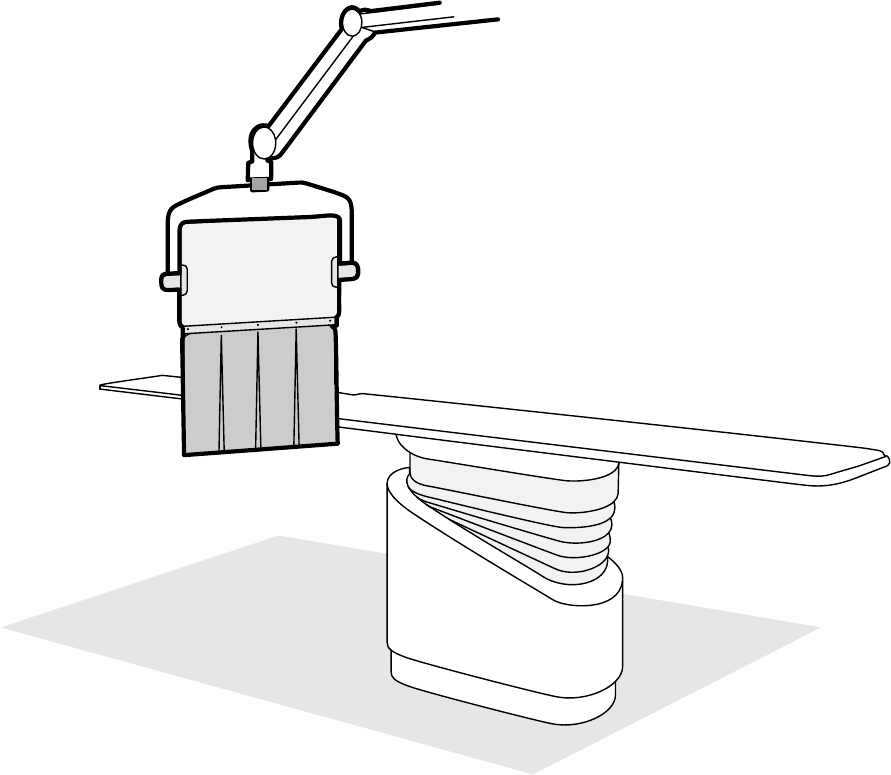

3.1.1 Ramię C.................................................................................................................. 26

3.1.5 Stół pacjenta.......................................................................................................... 31

3.1.6 Moduł sterujący..................................................................................................... 32